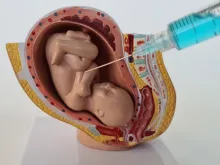

Comissão do Senado aprova projeto que proíbe aborto acima de 22 semanas mesmo nos casos previstos

A Comissão de Direitos Humanos (CDH) do Senado aprovou na quarta-feira (15) o projeto de lei que proíbe o aborto... Leia mais

Projeto de Lei propõe proibir cloreto de potássio em abortos tardios previstos em lei

Tramita na Câmara do Deputados um projeto de lei que veta o procedimento de assistolia fetal em casos de aborto... Leia mais